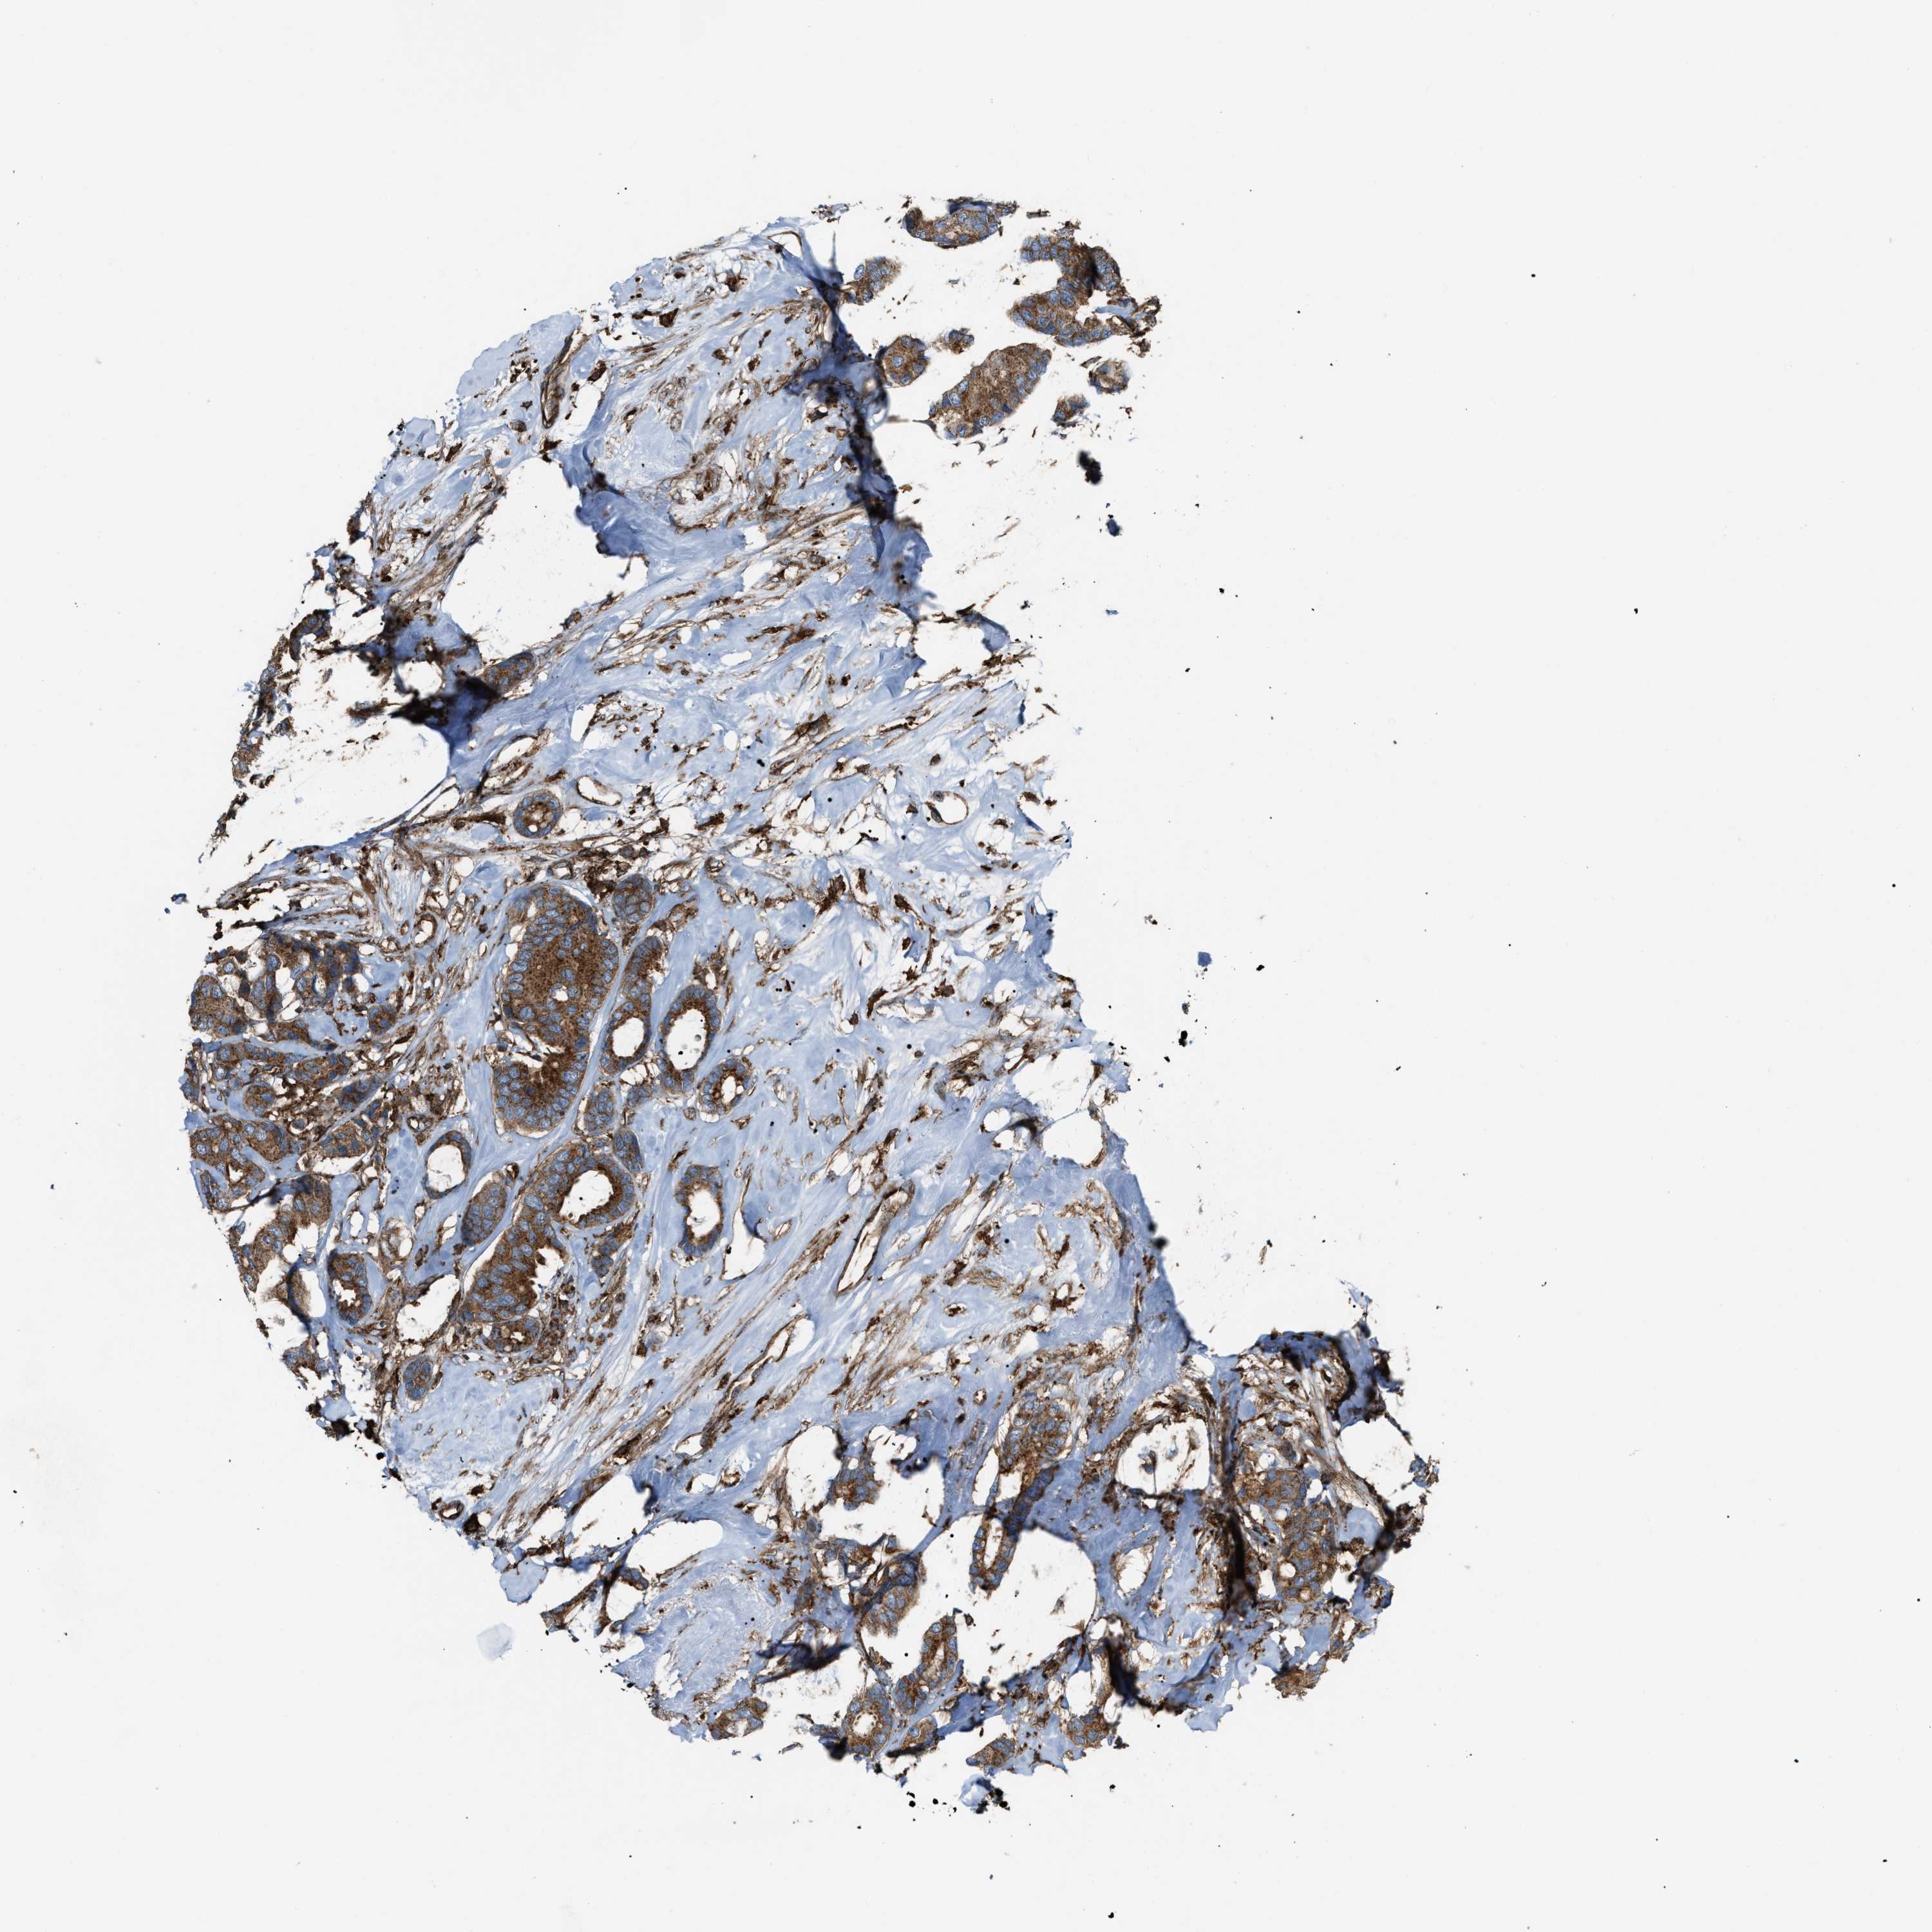

CANCER BREAST CANCER Show tissue menu

BRCA TCGA BRCA VALIDATION PROTEIN EXPRESSION